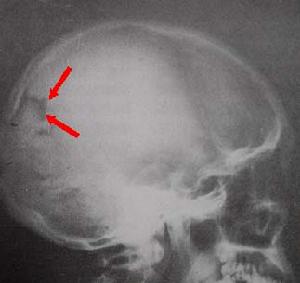

顱內占位性病變,常可通過影象學檢查獲得確診。影象學檢查包括頭顱CT掃描、核磁共振檢查及腦血管造影等。現代影象學檢查可顯示占位性病變的位置、大小、形態、數目,還能觀察到病變內部是否有囊變、壞死、鈣化、出血等。腦血管造影是根據血管的部位、形態的改變、循環時間的改變以及病理血管的出現等,間接了解病變的位置、大致形態、含血管是否豐富等。